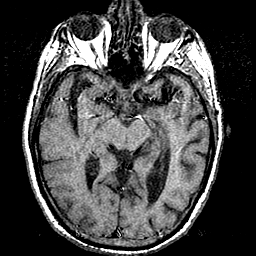

T1 - weighted MR -- Slice #20

[Home][Help][Clinical] Slice 20